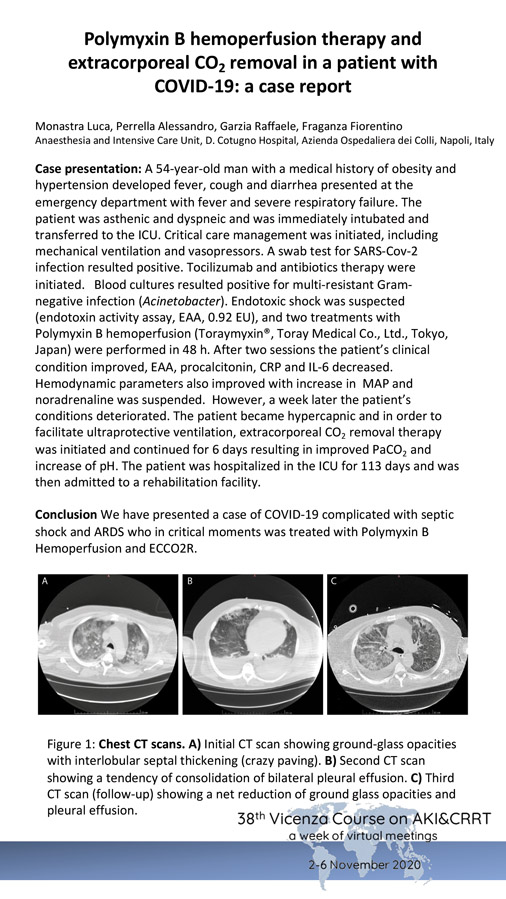

Monastra Luca